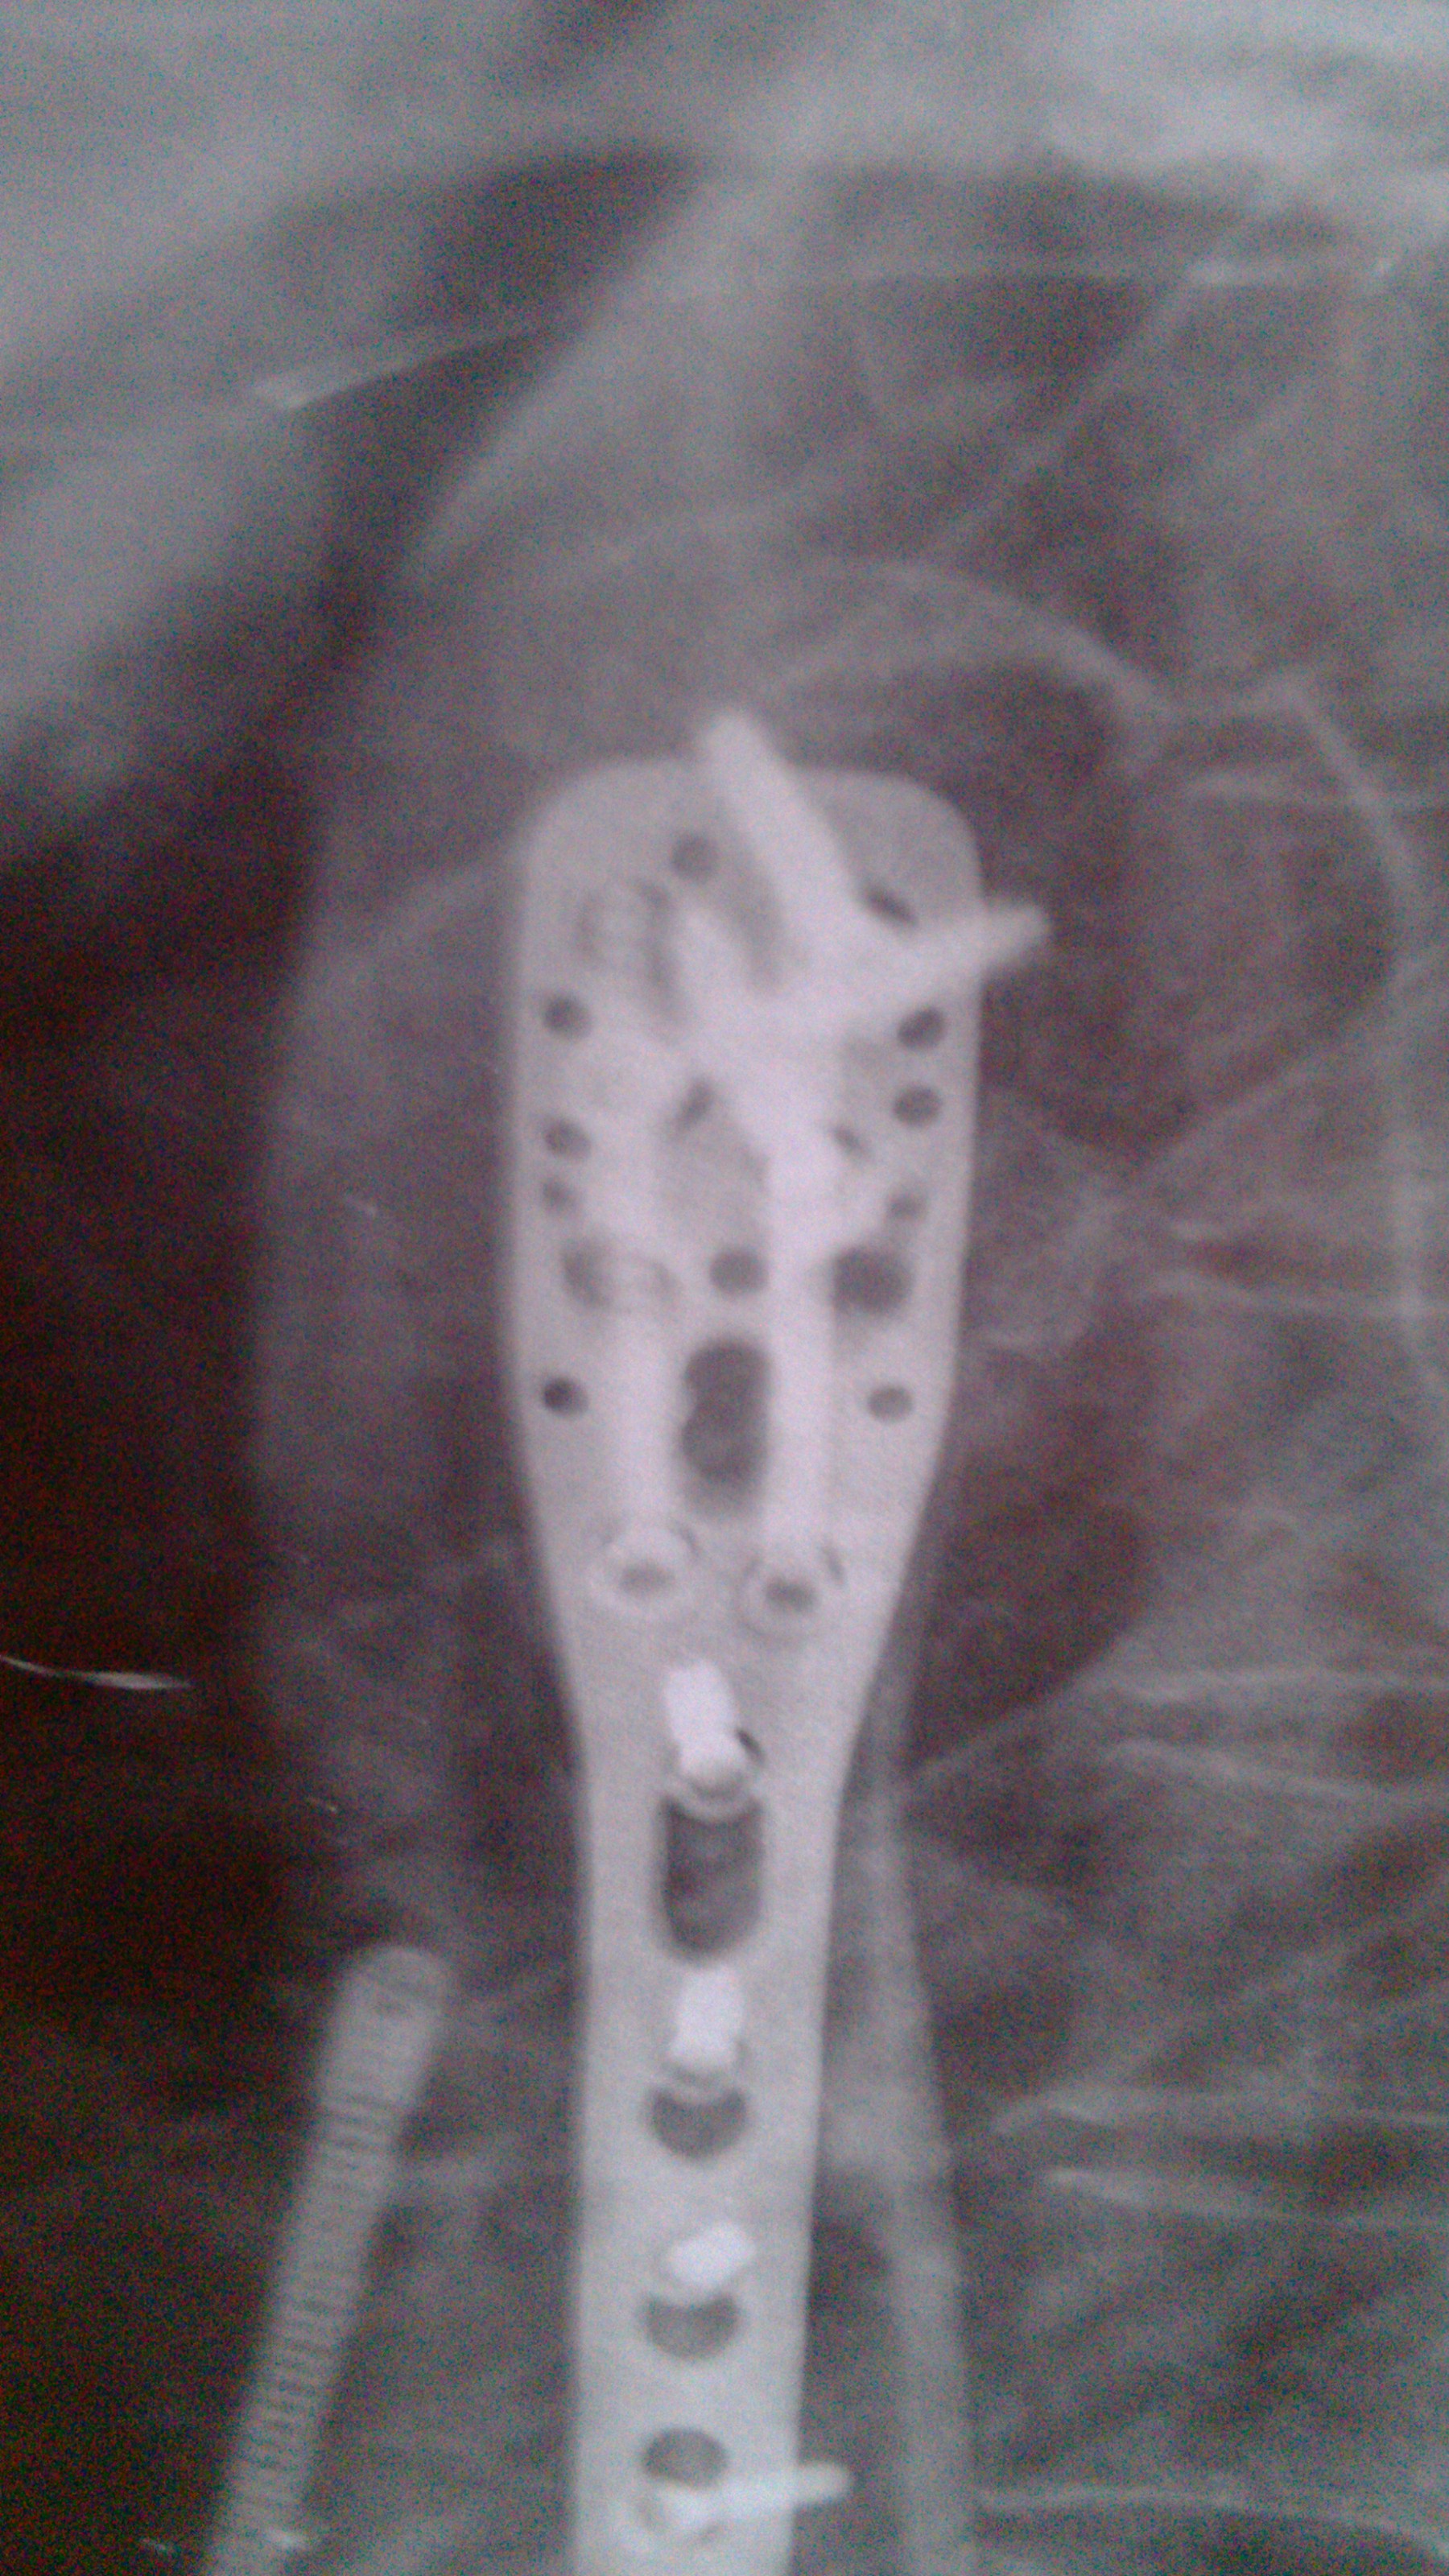

奥 奥德赛 声名鹊起 正式会员 注册 2012/11/14 帖子 197 获得点赞 1 声望 0 年龄 57 2013/06/04 #30 王家祥 说: 原方再服半个月。 点击展开... 王老师:你好! 自上次向你请教后,按原方服药又有一月,于昨日叫患者去照了一张片,现在我将这次照的片子发上来,请老师在百忙之中帮忙诊察一下,后续如何用药,如何治疗,还请老师指点,谢谢!!! 附件 6.3.jpg 1 MB 查看: 23 6..3.jpg 997.5 KB 查看: 25

王家祥 说: 原方再服半个月。 点击展开... 王老师:你好! 自上次向你请教后,按原方服药又有一月,于昨日叫患者去照了一张片,现在我将这次照的片子发上来,请老师在百忙之中帮忙诊察一下,后续如何用药,如何治疗,还请老师指点,谢谢!!!

王家祥 闻名全坛 正式会员 注册 2010/07/07 帖子 18223 获得点赞 403 声望 113 年龄 48 2013/06/05 #31 奥德赛 说: 王老师:你好! 自上次向你请教后,按原方服药又有一月,于昨日叫患者去照了一张片,现在我将这次 点击展开... 骨痂较上月好,可以配合内服补中益气汤!

奥 奥德赛 声名鹊起 正式会员 注册 2012/11/14 帖子 197 获得点赞 1 声望 0 年龄 57 2013/07/23 #37 王家祥 说: 骨痂较上月好,可以配合内服补中益气汤! 点击展开... 王老师,你好! 自上次向你咨询后至今已快两个月了,这两个月都一直在内服汤药配合丸药,并配合艾灸,今天又去重庆骨科医院摄了片,接诊医生叫继续服药。现在我将这次摄的片发上来,请老师帮忙诊断一下,下一步该如何进行?因为本病人骨折至今已近一年了,今后究竟该如何治疗,还望老师多多指教,在下替病人向王老师致谢谢了! 附件 IMG_20130723_184244.jpg 1.3 MB 查看: 28 IMG_20130723_183945.jpg 1.1 MB 查看: 27

王家祥 说: 骨痂较上月好,可以配合内服补中益气汤! 点击展开... 王老师,你好! 自上次向你咨询后至今已快两个月了,这两个月都一直在内服汤药配合丸药,并配合艾灸,今天又去重庆骨科医院摄了片,接诊医生叫继续服药。现在我将这次摄的片发上来,请老师帮忙诊断一下,下一步该如何进行?因为本病人骨折至今已近一年了,今后究竟该如何治疗,还望老师多多指教,在下替病人向王老师致谢谢了!

王家祥 闻名全坛 正式会员 注册 2010/07/07 帖子 18223 获得点赞 403 声望 113 年龄 48 2013/07/24 #38 奥德赛 说: 王老师,你好! 自上次向你咨询后至今已快两个月了,这两个月都一直在内服汤药配合丸药,并配合艾灸 点击展开... 片子不是很清晰,但可以看得出骨痂较前好。建议配合外敷药。可以用我的那个陈伤的药方。目的是温通局部。

奥德赛 说: 王老师,你好! 自上次向你咨询后至今已快两个月了,这两个月都一直在内服汤药配合丸药,并配合艾灸 点击展开... 片子不是很清晰,但可以看得出骨痂较前好。建议配合外敷药。可以用我的那个陈伤的药方。目的是温通局部。